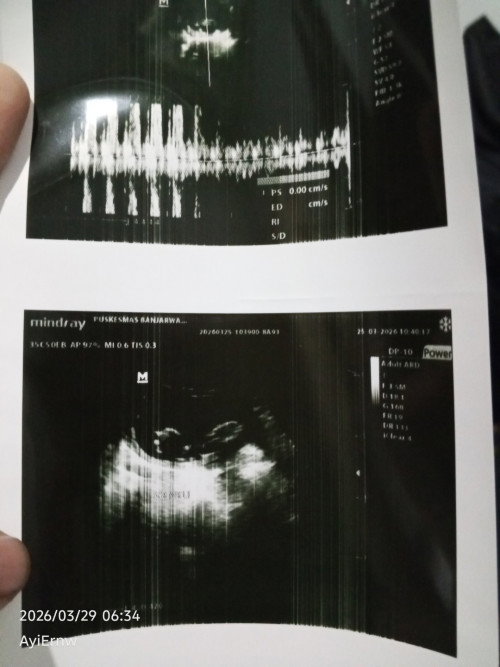

Hasil USG

Mom saya kan USG di kehamilan 10-11 Minggu dan ini hasilnya ada 2kantong beserta janinnya dan 2djj yang sudah terdeteksi dengan jelas kata dokter nya sih kembar ya mom, saya mau tanya apa ada kemungkinan hasil USG salah atau sudah akurat ya mom? #mohonbantujawabbunda #Sharingdong_Bund